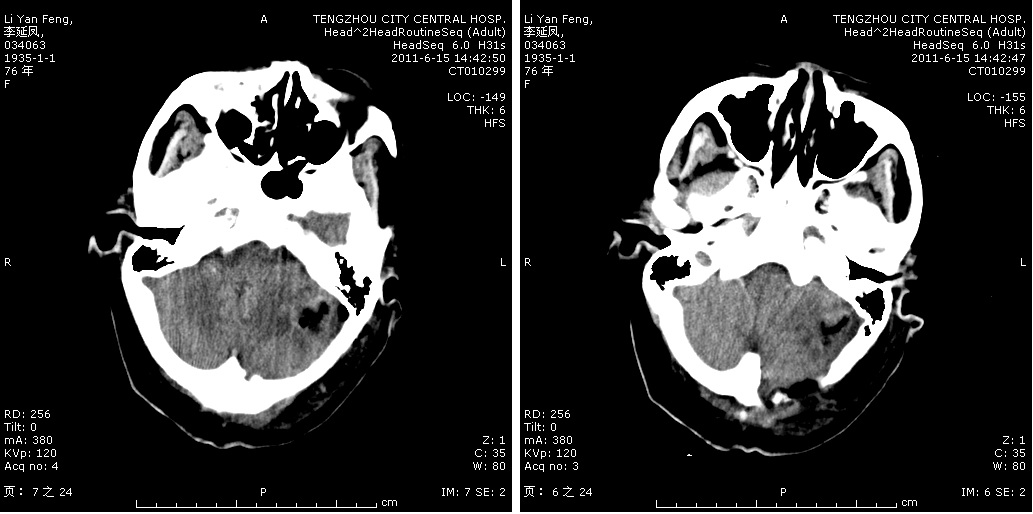

轉(zhuǎn)移瘤切除術(shù)前

轉(zhuǎn)移瘤切除術(shù)后